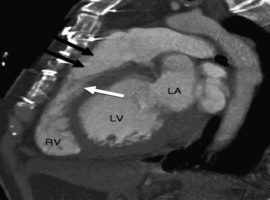

Right Atrial Metastasis from Hepatocellular Carcinoma Leading to Submassive Pulmonary Embolism: An Uncommon Clinical Presentation

Van Loo AM*, Rempakos A, Fisher SRD, et al. (USA)